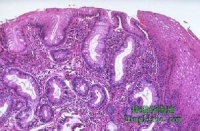

显微镜下,病变部位的黏膜充血,黏液腺管扩张内含多量稠厚的黏液,黏液排出后参与假膜的组成,病变重时绒毛和黏膜顶部有不同程度的坏死或消失。固有层中有中性粒细胞、浆细胞和淋巴细胞浸润,腺体断裂坏死。黏膜下层毛细血管扩张、充血及血栓形成,血管壁坏死可导致黏膜缺血坏死。病变一般仅限于黏膜层,但也可以向黏膜下层扩展累及全层,甚至导致大片坏死。一般可按病变程度分成轻度、重度、严重3型:

①轻度病变:最初的损害是在黏膜的固有层中出现急性炎性细胞、嗜酸性粒细胞浸润和纤维素渗出,形成灶性坏死。在坏死的病灶中的纤维蛋白原和多形核细胞聚集形成特殊的顶极损害。

②重度病变:病变未侵犯到黏膜下层,黏膜腺体被破坏,假膜形成。含有黏蛋白的急性炎性细胞的破坏和腺体被典型的假膜所覆盖,固有层中性多形核细胞浸润,伴有典型火山口样隆起坏死病变。

③严重病变:黏膜完全破坏,固有层深层受到侵犯,黏膜固有层被一层厚而相互融合的假膜覆盖。